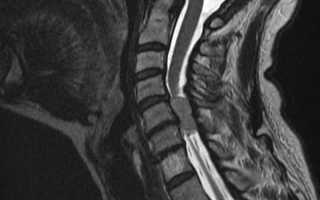

Если специалист обнаружит какие-либо отклонения, он направляет пациента на дополнительные исследования. Обычно менингиома позвоночника выявляется с помощью следующих методов диагностики:

- МРТ.

- КТ.

На сегодняшний день наиболее точным методом диагностики считается МРТ, однако стоимость этой процедуры достаточно высока.